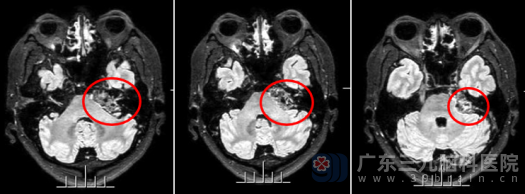

随着症状加剧,杨先生最终下定决心,来到广东三九脑科医院神经外十科寻求进一步治疗。术前头颅MR详细显示:左侧桥小脑角区有一个约32×20×19mm的团块状病变,信号不均匀,增强后未见明显强化——这典型的影像表现指向了表皮样囊肿(胆脂瘤)的特征。这种囊肿虽多为良性,但生长在关键脑区,可能压迫、包裹神经,引发头痛、头晕、听力下降甚至面瘫等症状,确实不容小觑。面对这个“沉默的杀手”,外十科医疗团队迅速制定了周密的手术方案。

手术当天,神经外十科团队凭借精湛的技术和丰富的经验,前后历时6个小时,成功切除了囊肿(胆脂瘤)。术中,医生在显微镜放大下小心翼翼地避开周围重要的神经和血管,确保最大程度保护小脑、脑干及颅神经功能,雕刻式全切肿瘤。术后复查头颅MR显示:左侧桥小脑角占位病变已完全切除。病理报告进一步确认了诊断:符合表皮样囊肿。杨先生恢复顺利,神志清醒,对答切题,已能自主进食和活动,不久后便康复出院。